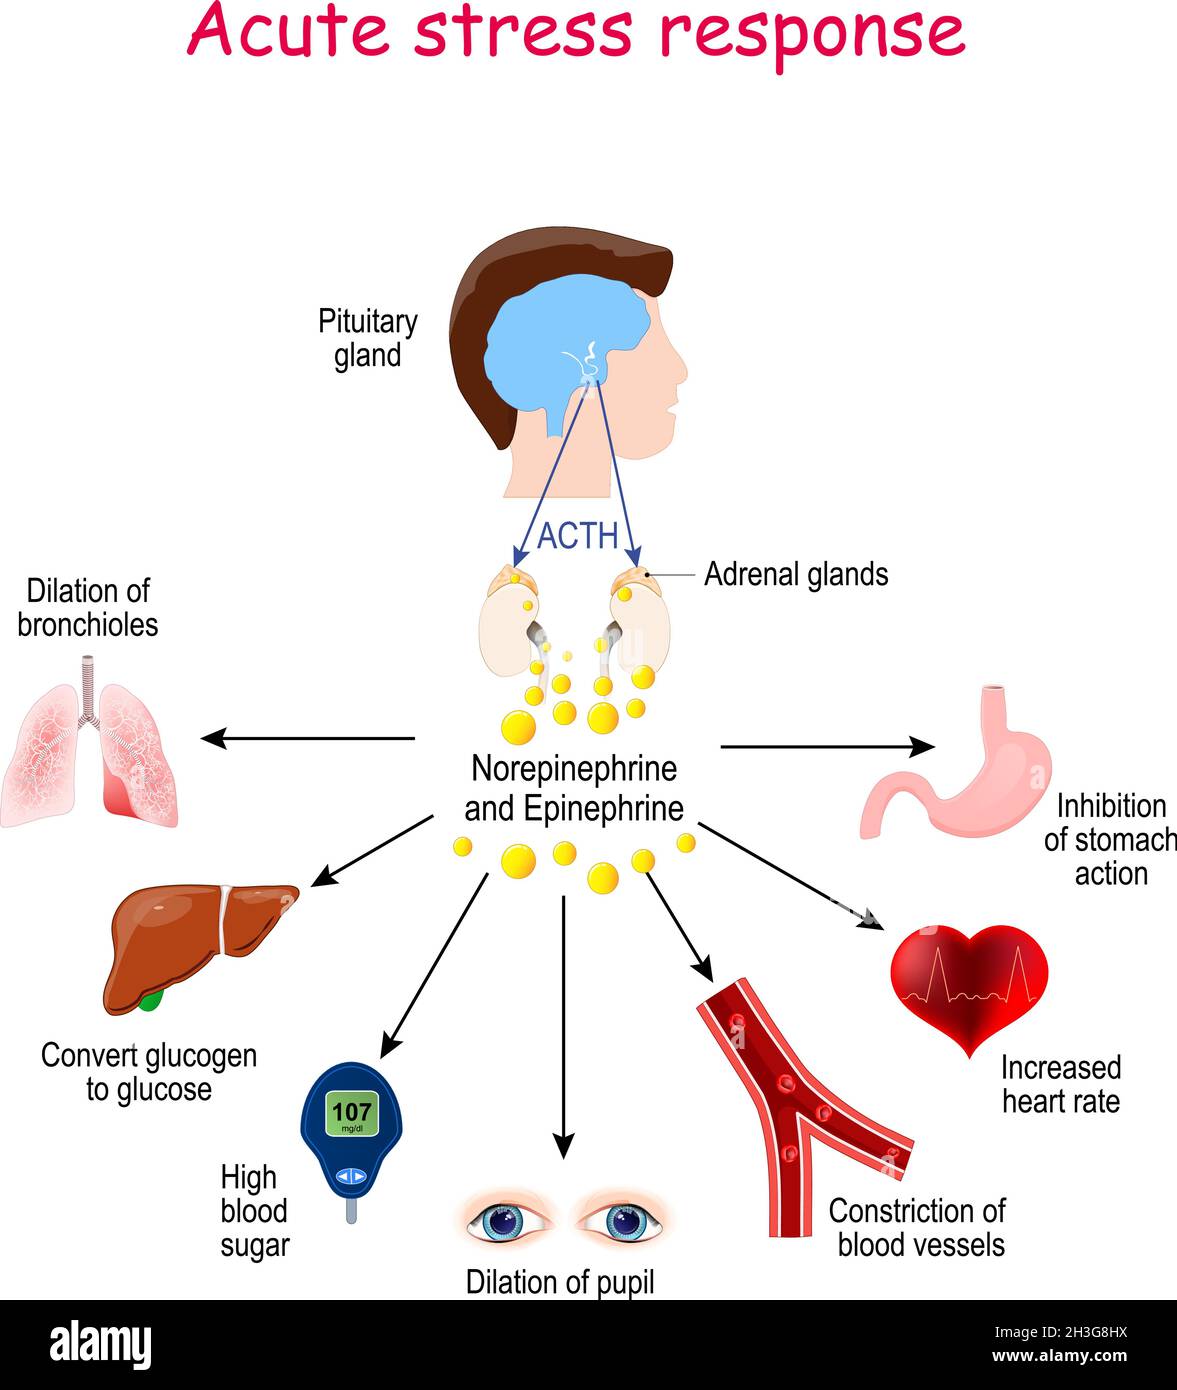

Acute stress response. Reaction of endocrine system. Hormones (Norepinephrine, Epinephrine, ACTH), and Target organs (heart, lungs, liver, eyes, blood Stock Vectorhttps://www.alamy.com/image-license-details/?v=1https://www.alamy.com/acute-stress-response-reaction-of-endocrine-system-hormones-norepinephrine-epinephrine-acth-and-target-organs-heart-lungs-liver-eyes-blood-image449671542.html

Acute stress response. Reaction of endocrine system. Hormones (Norepinephrine, Epinephrine, ACTH), and Target organs (heart, lungs, liver, eyes, blood Stock Vectorhttps://www.alamy.com/image-license-details/?v=1https://www.alamy.com/acute-stress-response-reaction-of-endocrine-system-hormones-norepinephrine-epinephrine-acth-and-target-organs-heart-lungs-liver-eyes-blood-image449671542.htmlRF2H3G8HX–Acute stress response. Reaction of endocrine system. Hormones (Norepinephrine, Epinephrine, ACTH), and Target organs (heart, lungs, liver, eyes, blood